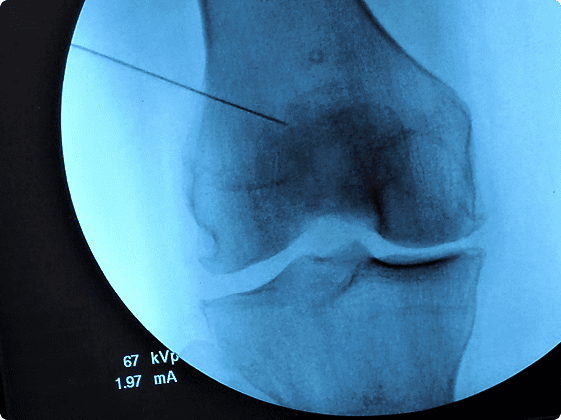

The response to cortisone injections is variable and unpredictable. In order to give the medication a chance to reduce the inflammation, please perform only moderate activity until any discomfort resolves.

For injections in the lower extremity please refrain from excessive walking, kneeling, squatting. For injections into the shoulder or elbow, please refrain from excessive throwing, weight lifting, any repetitive or strenuous activities.

The medicine in the injection has a local anesthetic and will wear off in a few hours. The medicine in the injection also contains cortisone to reduce the inflammation and this will begin working after 1–2 days.

The response to viscosupplementation can take up to one month after the injections and the duration of relief is variable. The medication syringes come pre-packaged and are used according to the manufacturer’s instructions. There is a small incidence of injection site pain that is usually mild and responds to rest and ice.